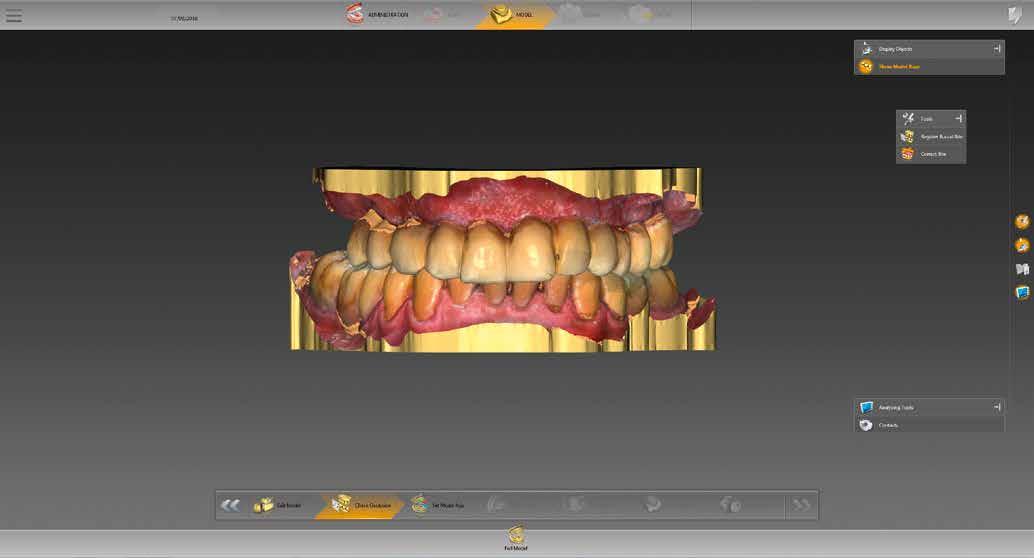

3–4. ábrák: Ellenőrizzük az érintkezési pontok egyensúlyát.

szükséges információ rögzítésére megfelelt. A meglévő pótlásról is készült egy ún. BioCopy-Scan (1. ábra), amelyet összevetíthetünk a felső állcsontról készült, az adhezív sapkákat is tartalmazó beolvasással (Atlantis Conus Abutment, Dentsply Sirona). Így meghatározhattuk a vesztibuláris szituációt és a vertikális helyzetet, ami megkönnyíti a funkcionális és esztétikai szempontból is kiemelkedő munka elkészítését. Ellenőriztük a meglévő pótlás egyensúlyát és érintkezési pontjait (3–4. ábrák), meghatároztuk a minta tengelyét (5. ábra), majd az adatokat az inLab szoftverbe importáltuk.

A tényleges munkát megelőzte a restauráció típusának kiválasztása. Kipipáltuk a multilayer és gingiva szavakat (6. ábra). Ezenfelül három hidat (14-16, 13-23, 24-26 régió) jelöltünk be, amelyek később a tercier részek lesznek. A „Modell” munkafázisban külön-külön megnézhettük a maxilla és mandibula mintáját (7. ábra), és ellenőrizhettük az intermaxilláris távolságot (8. ábra). A BioCopy alapján pontosan állíthattuk be a két mintát egymáshoz képest (9. ábra). Ezt követte egy nagyon fontos lépés: a felső állcsont gerinc-középvonalának berajzolása (10.

9. ábra: A BioCopy szkennelés alapján illesztjük a felső és alsó mintát. 6. ábra: Az adminisztratív fázisban meghatározzuk az alapbeállításokat, aktiváljuk a „multilayer” és „gingiva” mezőket.

8. ábra: Az intermaxilláris távolság ellenőrzése.